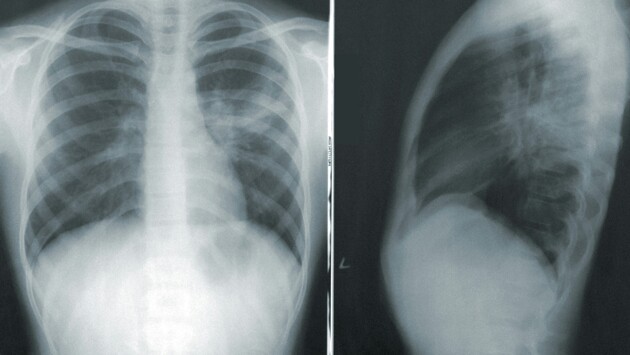

Терапевт назвал отдышку первым симптомом «серьёзного» поражения лёгких

О развитии пневмонии также свидетельствуют высокая температура и сильная слабость.

«Люди должны знать, что если у них развиваются симптомы ОРВИ, нужно хотя бы сделать экспресс-тест. Если это COVID-19, обязательно связаться с врачом для того, чтобы он успел назначить как можно быстрее противовирусные средства, если есть показания. Первое, конечно, одышка. Если она развивается, это может свидетельствовать о серьёзном поражении лёгких. Очень сильная общая слабость, температура выше 38,5. Разные серьёзные болезни, которые есть у пациентов — это диабет, ожирение, сердечная недостаточность, ишемическая болезнь сердца, поражение почек, то здесь общий профиль риска очень важный. Есть специальные шкалы, по которым можно посчитать это всё, уровень сатурации ещё учесть. Его падение ниже 95 и тем более ниже 93 — это важно».